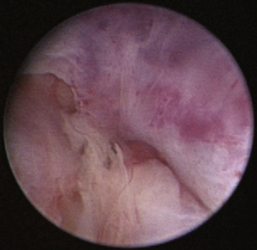

Normal turbinates have a smooth, pink-to-white surface and a spatial alignment that provides channels for the passage of air. The color varies and appears tan in the caudal nasal cavity. Turbinates come in different shapes and sizes, but the surface should be smooth. Ethmoid turbinates in the caudal nasal cavity will have a characteristic stippled or corrugated appearance (Figures 19-13 through 19-16). Ulcerations or various proliferations of the mucosa are indicative of disease. These changes are typically diffuse and accompanied by a lot of mucus. Mucus can be thin to purulent. Copious amounts can be flushed out of the nasal cavity to allow better visibility. The specific disease is determined by biopsy. After full examination of the nasal cavity, run the scope along the floor of the nasal sinus to the level of the choanae. Keeping the scope pointed in a ventral medial direction prevents inadvertent trauma or penetration of the cribriform plate. The index finger of the free hand can be used to follow the scope as it moves caudally over the hard palate; the surgeon can then palpate the scope through the soft palate when it moves into the nasopharynx. Some force is needed to complete this procedure and may result in increased bleeding.

image

Figure 19-13 Normal canine rostral nasal cavity; the septum is medial (left).

Figure 19-14 Normal canine meatus division.

Figure 19-15 Normal canine nasal turbinate mucosa.

Figure 19-16 Normal canine ethmoid turbinate.